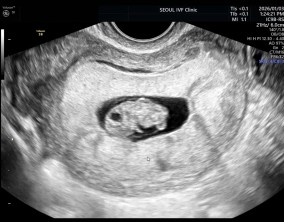

심장소리 이후, 함께 웃게 된 임밍아웃

유정원장님 치료 과정 내내 항상 따뜻하게 진료해 주셔서 감사한 마음이 큽니다. 덕분에 불안한 순간에도 마음을 다잡고 치료를 이어갈 수 있었습니다.